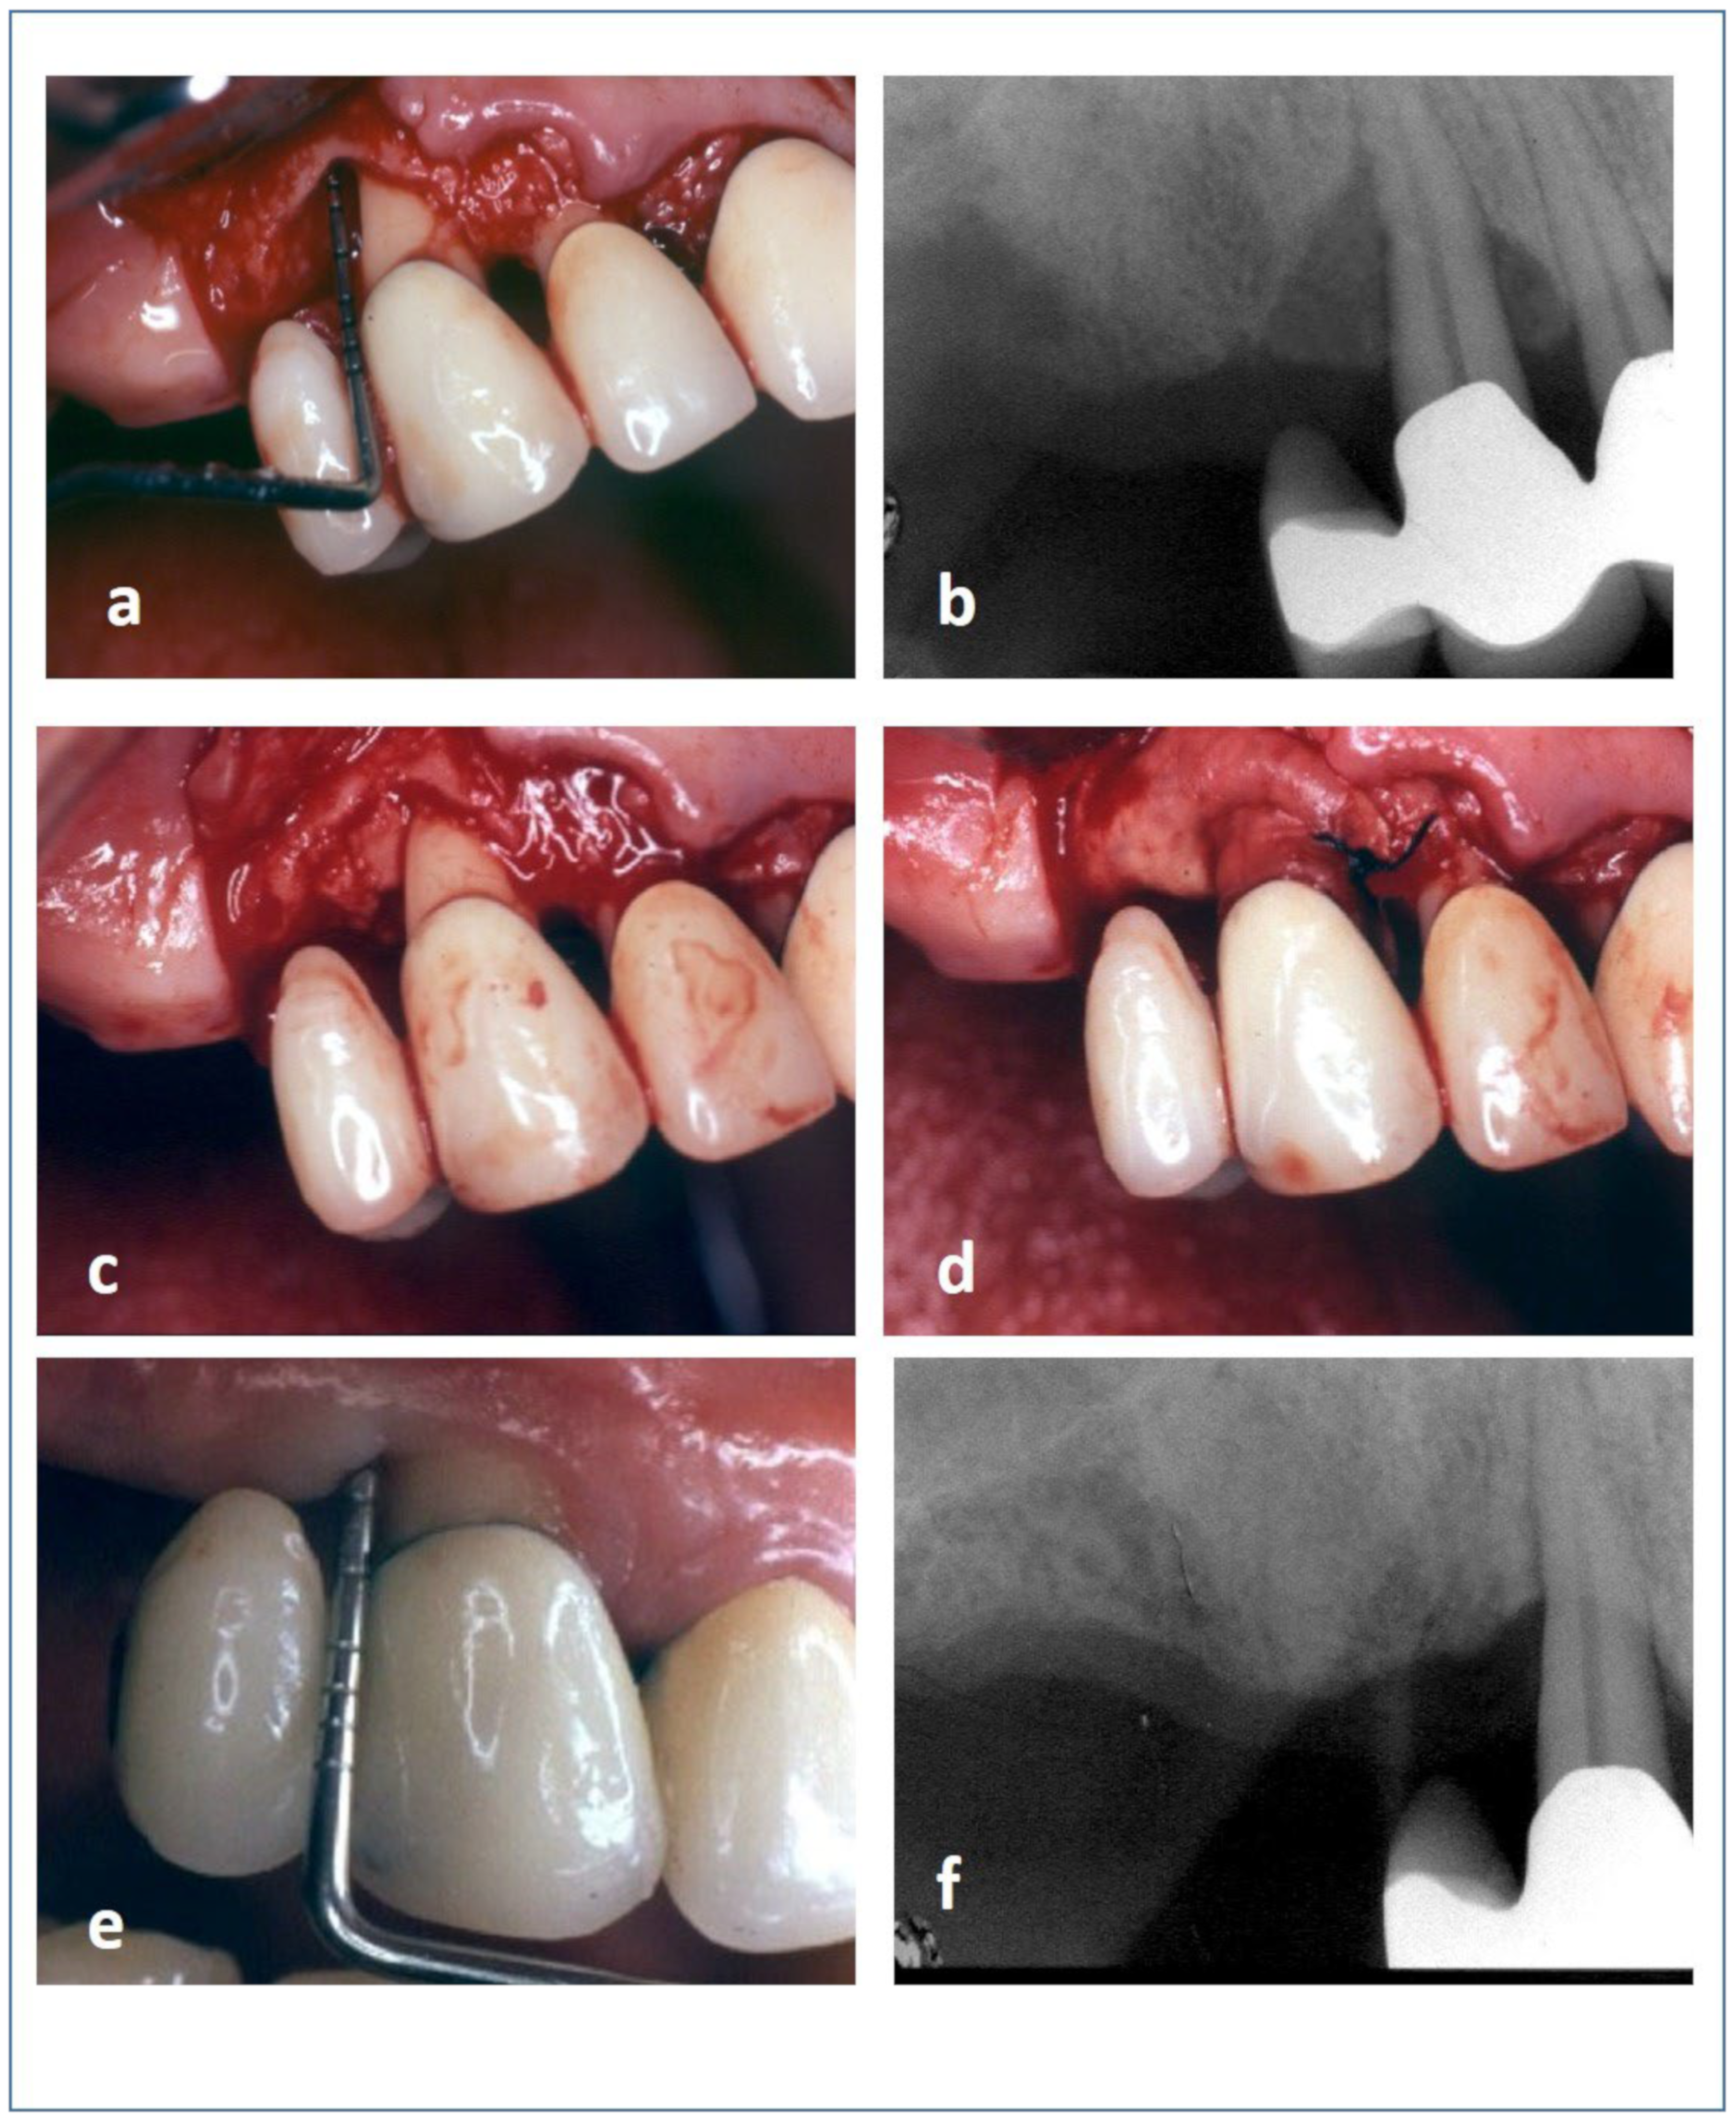

2.9. Surgical Procedure

3. Results

3.2. Clinical and Radiographic Outcomes